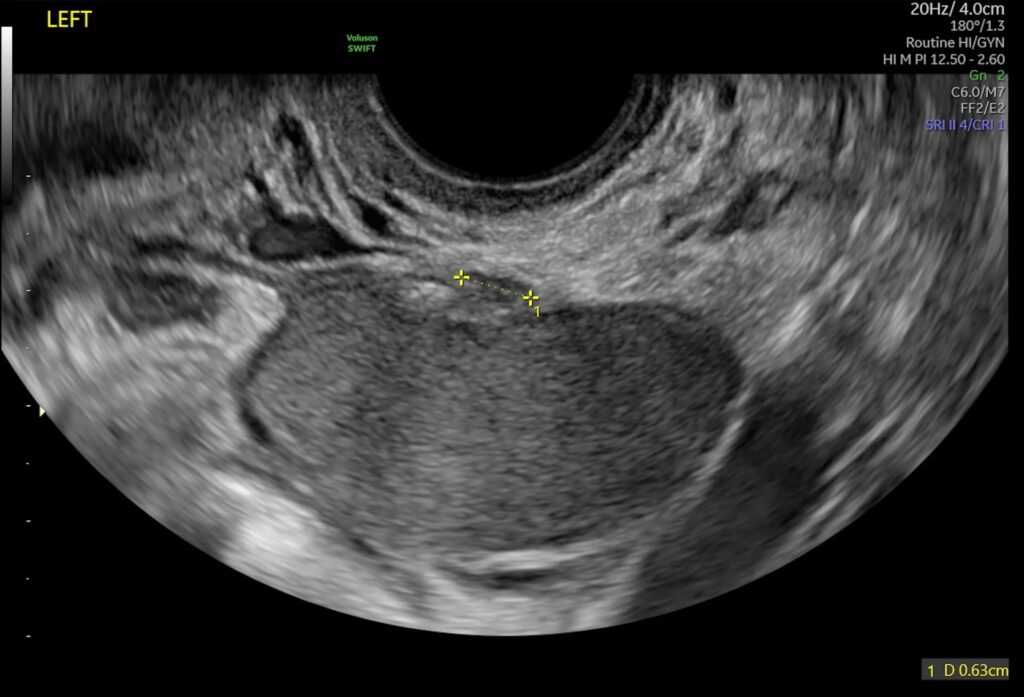

- Ovarie-endometriose (Endometriomer): Her vokser endometriosevævet inde i æggestokkene og danner cyster fyldt med gammelt blod, ofte kaldet 'chokoladecyster'. Disse er generelt lettere at identificere på en ultralydsscanning.

En ultralydsscanning bruger lydbølger til at skabe billeder af kroppens indre organer. Til at undersøge for endometriose anvendes en transvaginal ultralyd, hvor en slank probe føres ind i skeden. Dette giver de klareste og mest detaljerede billeder af bækkenorganerne. Selvom det kan være ubehageligt, især hvis man har smerter, er proceduren sikker og tolereres generelt godt.

- Vurdering af livmoder og æggestokke: Først undersøges livmoderen for tegn på adenomyose og æggestokkene for endometriomer.